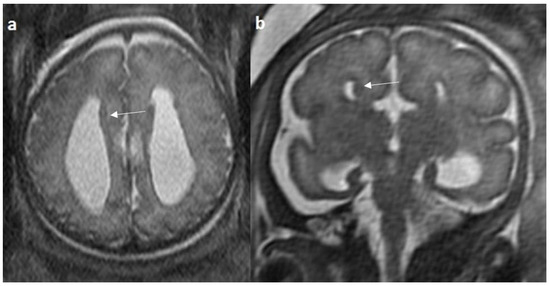

Colpocephaly is seen in 13/24 cases (54%) (Figure 5). Of them, 12 cases had complete agenesis, and one case had hypoplasia. Absent septum pellucidum is seen in 5/24 cases (20.8%) (Figure 6); 4 cases had complete agenesis, and one case had hypoplasia. Probst bundles are identified only in the isolated form of CCA and account for 3/19 cases (15.7%) of complete agenesis and 3/4 cases of the isolated form of CCA (Figure 7). Probst bundles are not seen in other subclasses of CCA. Ventriculomegaly is seen in 7/24 cases with an incidence rate of 0.29%, 5 cases had complete agenesis, and 1 case each had hypoplasia and hypoplasia with dysplasia.

Figure 7.

Fetal MRI images of a 20 gestational weeks aged fetus with complete agenesis of the corpus callosum. (a) A T2-weighted sequence image in axial plane showing non-decussating anterior-posterior white matter tracts known as Probst bundles medial to the lateral ventricles (arrow). (b) A T2- weighted sequence coronal image showing Probst bundles indenting superomedial margins of lateral ventricles. Probst bundles are seen with complete agenesis of the corpus callosum.